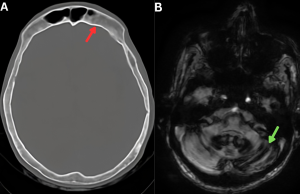

Fig 11: Figure A: Bone-window CT of the skull shows calvarial cortical thickening (red arrow), consistent with osseous changes associated with chronic low cerebrospinal fluid pressure.

Figure B: Axial SWI images show hypointense curvilinear susceptibility artifacts along the cerebellar folia and the brainstem surface, consistent with hemosiderin deposition (green arrow), suggestive of superficial siderosis.